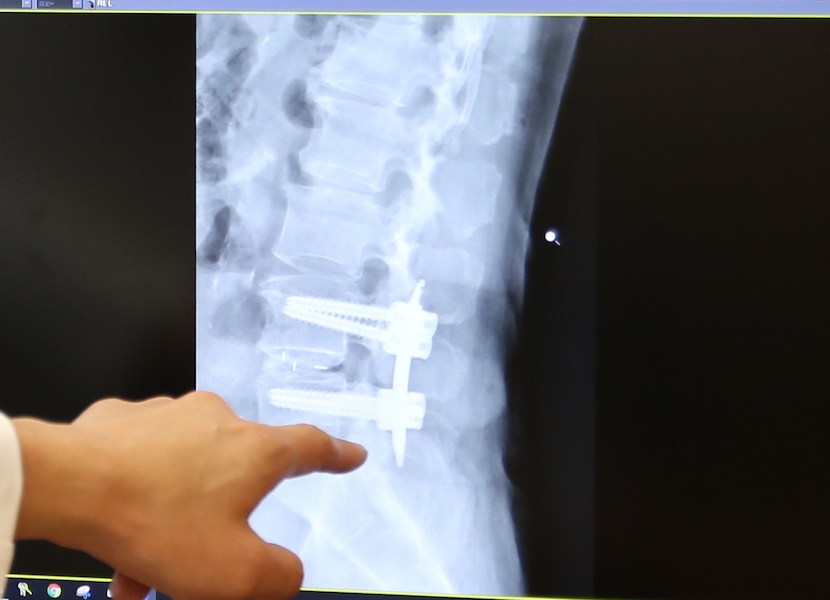

用在改善腰椎滑脫的腰椎融合手術,須植入鋼釘與支架來穩定脊椎。

因此,全球脊椎手術專家凝聚共識開創腰椎微創手術,經十多年發展已技術成熟,漸為治療主流。微創手術目的在於減少對正常組織的破壞,進而減少術後慢性疼痛,以最常施行的腰椎融合手術來說,用在腰椎滑脫的改善,須植入腰椎鋼釘與支架來穩定脊椎,微創經皮鋼釘植入手術可以經由更小的傷口完成一樣的工作,沒有大區域的肌肉韌帶破壞,病人術後慢性疼痛的問題大幅減少。